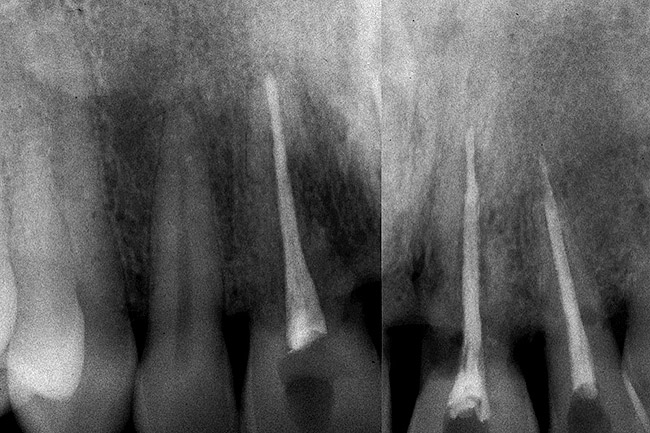

Figure 6  Excellent interproximal crestal bone level between the centrals before extraction.

Figure 6

Figure 10  In these adjacent implants placed in the central and lateral positions, note the excellent interproximal bone but minimal interimplant distance.

Figure 10